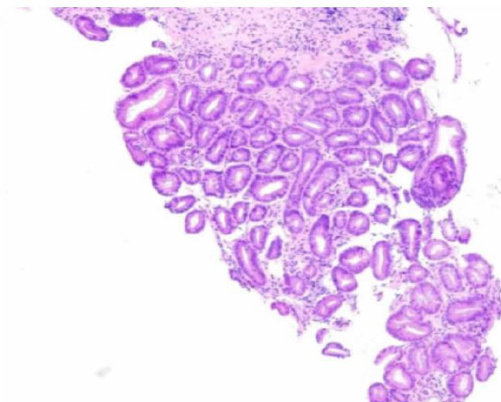

胃癌是一种常见的恶性肿瘤,其早期诊断和治疗至关重要。在我国为了提高早期胃癌的诊断准确性和治疗效果,我们通常借鉴了日本的诊断器械和内镜切除早期癌的方法。(剩余13147字)

早期胃癌诊断中日本标准与WHO标准的对比研究